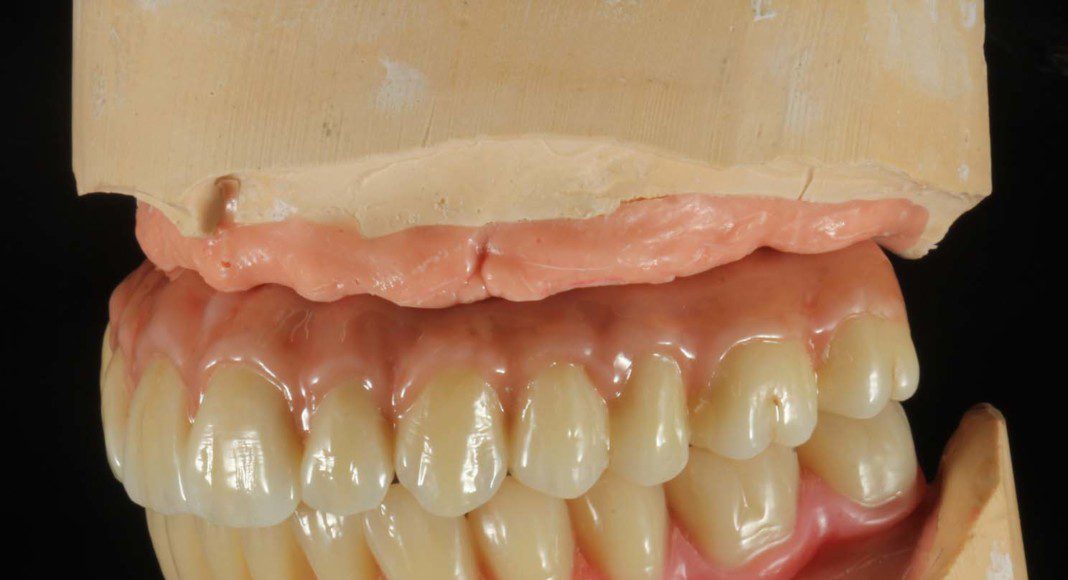

Polyvinylsiloxane is used (pink material) to recreate the soft tissues on the implant model. Laboratory analogs are placed by screwing them into the impression copings.

This is the upper, wax-up used to determine final tooth position and bite. At the patient’s request, the teeth were made slightly irregular. These are denture teeth selected for size and shape based on a combination of his temporaries and his and his wife’s requests. These are NOT the final color.

Even in the wax-up you can see the convex contour of the part of the prosthesis that touches the tissue. This is of paramount importance for cleaning. The visible cylinders are the connection to the implants. Frontal view with slightly superior angle.